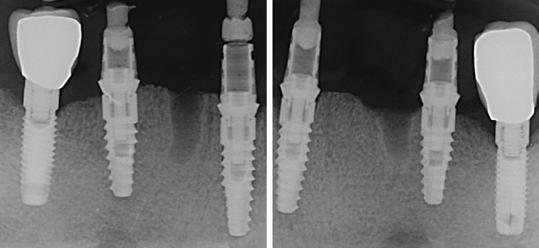

17. kép: Intraorális szkenneléshez pozicionált szkennelőfejek az implantátumokon.

18-20. kép: 3shape intraorális szken felvételek a sebészetet követően.

Egy héttel a műtét után – az ideiglenes híd behelyezve, pozícióban (39-41. kép). A digitális röntgenfelvétel mutatja az implantátumok szögeit és az elhelyezésüket (42. kép). Periapikális felvétel az ideiglenes híd illeszkedésének ellenőrzésére (43. kép). Végső kép az alsó implantátumos hídról a páciens szájában. Elejétől a végéig 3 ülésben.